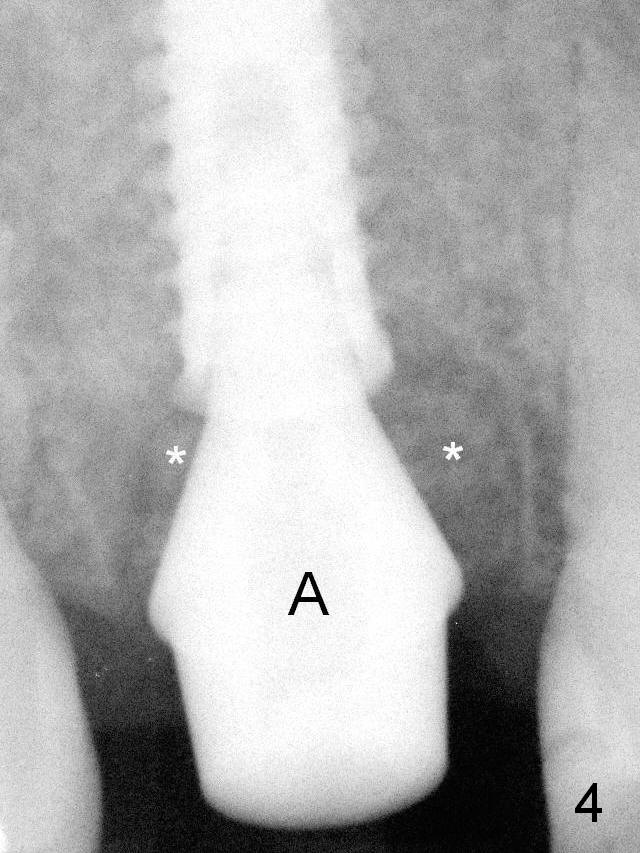

The implant was placed deep enough without thread exposure; now with apparently complete abutment seating (Fig.11). The similar complication may recur due to refusal to have implant at #19 (fear of nerve injury).